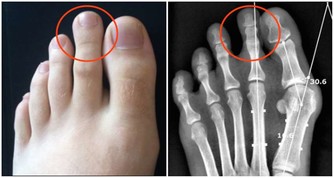

1、肝癌早期有隱秘性,關注7個症狀

- 出血症狀(牙齦出血、皮下瘀斑等)

- 肝區疼痛